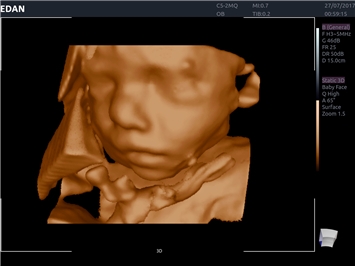

EDAN Acclarix AX8

Новая эра общей ультразвуковой визуализации. Новый взгляд на инновации — улучшенная производительность при более низких затратах Несмотря на компактную конструкцию, AX8 представляет собой ультразвуковую диагностическую систему премиум-класса с передовыми технологиями визуализации, которая обладает полным набором функций.

EDAN Acclarix AX8 представляет собой компактную высокотехнологичную ультразвуковую систему, сочетающую передовые технологии визуализации с интуитивно понятным управлением и улучшенной мобильностью.